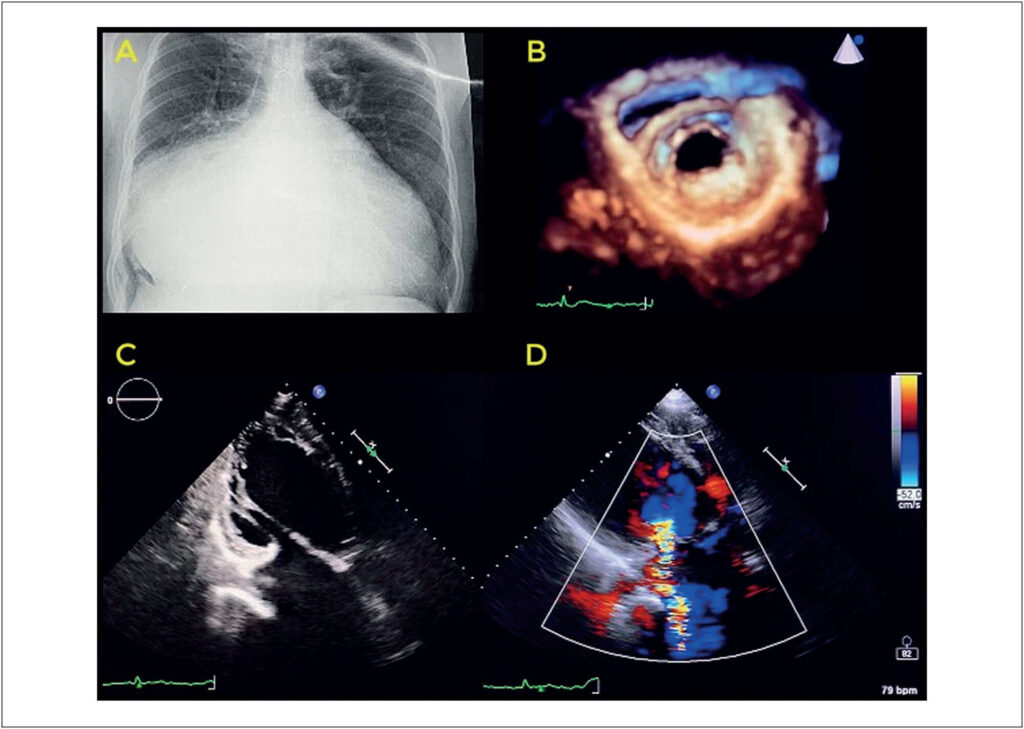

Giant Left Atrium due to Probable Rheumatic Disease and Atrial Functional Mitral Insufficiency

Giant left atrium is a rare condition, and most cases described in the literature are associated with rheumatic disease. However, some clinical descriptions suggest a nonrheumatic etiology for this condition, in which characteristic findings of rheumatic disease are not identified or anatomopathological findings do not suggest a specific etiology.

Atrial fibrillation is present in almost all cases and contributes to the maintenance of left atrial remodeling and persistent changes in structure and function.